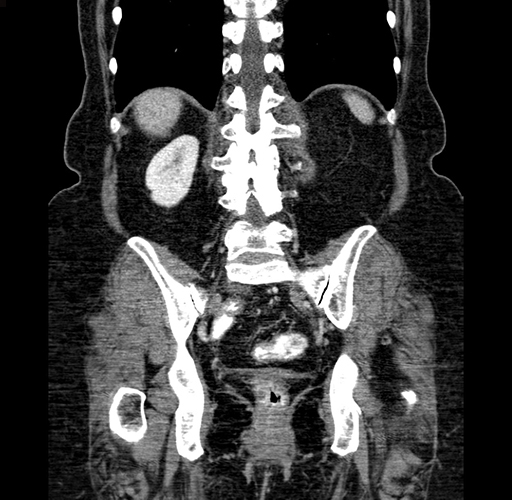

Coronal Venous